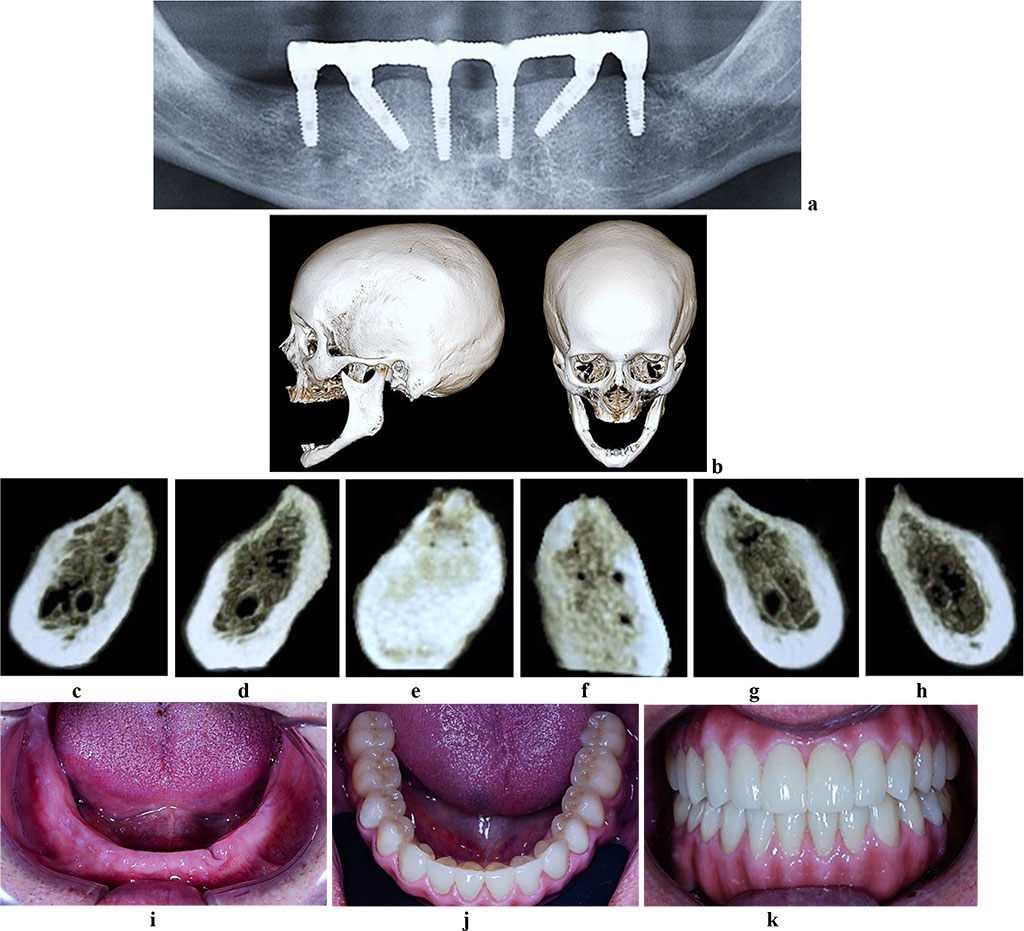

Figure 8. Patient S., 62 y.o. Diagnosis: lower jaw total adentia; Class I by Keller. Lower jaw CBCT: a – bone tissue 12 months following the installation of dental implants (panoramic reformat); b – volume rendering; 3D cross-sections at the adentia area 3.2 (c), 3.4 (d), 3.6 (е), 4.2 (f), 4.4 (g), 4.6 (h) prior to the installation of dental implants; lower dentition before (i) and after (j, k) implantological and prosthetic treatment.

The CBCT of the cross-sectional 3D window at the area of planned dental implantation in the main group revealed minor changes in the bone tissue microarchitectonics, while the amount of bone was maintained. The 3D window of volumetric rendering mode showed that at the area of dentition defects, the cortical bone was wide and intact throughout. There were some minor qualitative changes observed in the spongy bone: the spongy bone trabeculae width and the bone trabeculae structure density were slightly reduced; there were some spots identified where the intertrabecular space was expanded; the vestibular and lingual cortical plates were intact; the trabecular structure preserved its integrity yet there was a slight change in the structure arrangement (disorientation) observed in the bone trabeculae (Fig. 6-8).